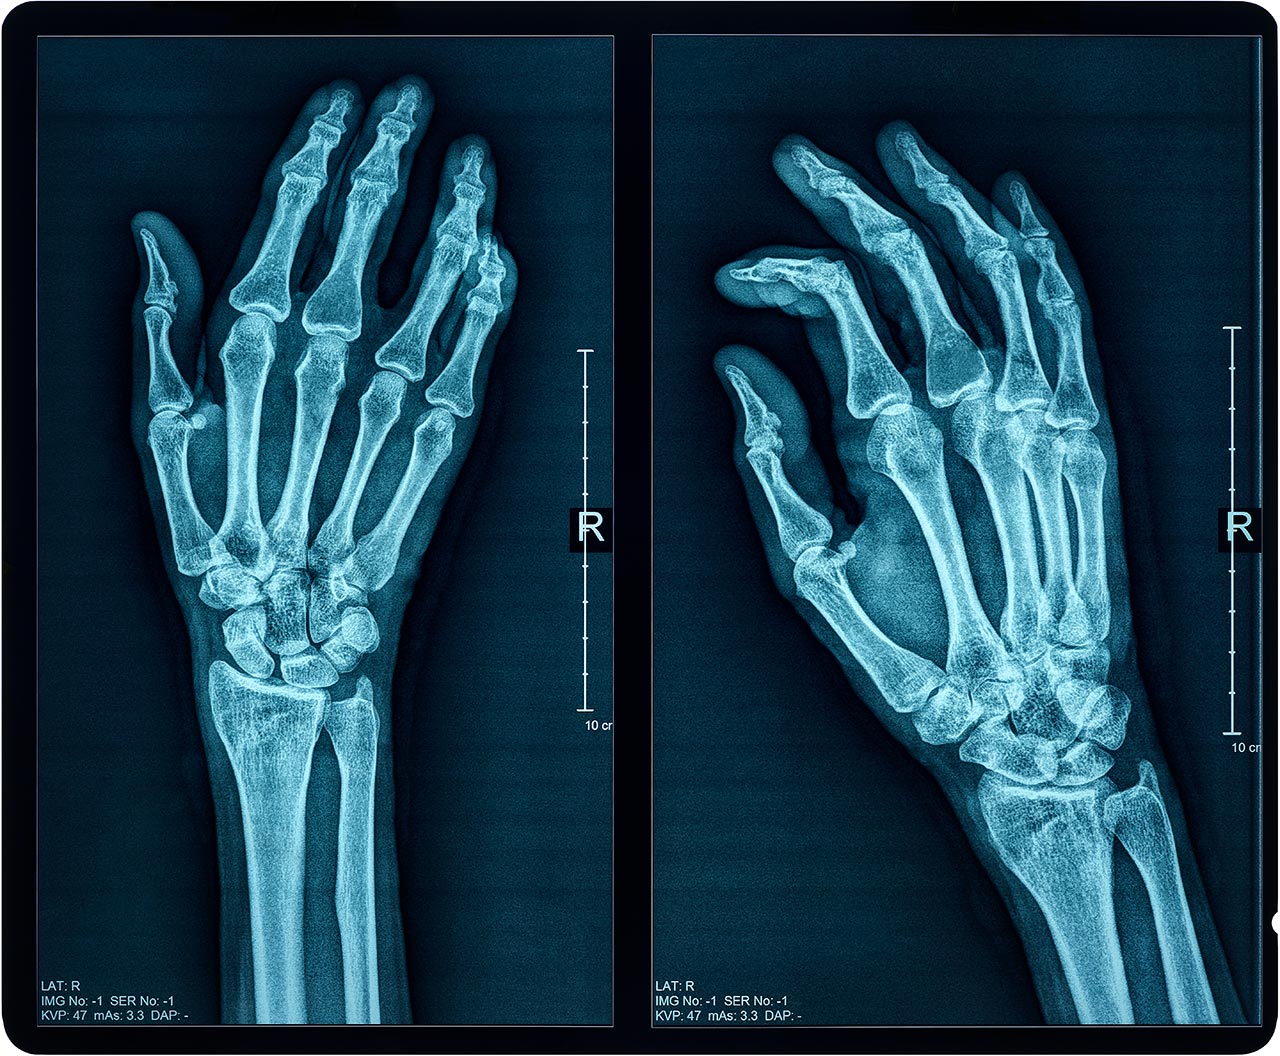

Vďaka vysokej prenikavosti sa röntgenové žiarenie široko využíva v medicíne na zobrazenie vnútorných štruktúr ľudského tela a v priemysle napríklad na kontrolu zvarov. Keďže ide o ionizujúce žiarenie, môže pôsobiť na živé tkanivá. Presne zamerané intenzívne röntgenové žiarenie sa využíva aj v onkologickej terapii.